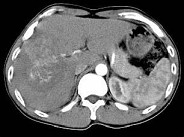

- 单项选择题根据所提供的图像,最可能的诊断是 ( )

A、肝血管瘤

B、FNH

C、肝癌

D、肝腺瘤

E、以上都不是